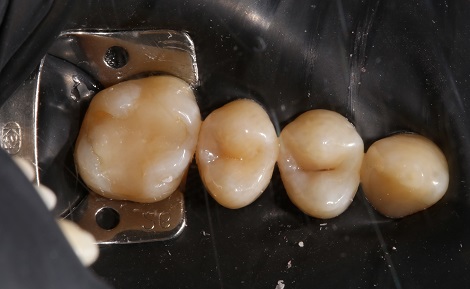

Пломбування кореневих каналів.

Якісно запломбовані кореневі канали є основою

довговічності. Тому очищення і пломбування кореневих каналів в «Домі Стоматології»

приділяється особлива увага! Після пломбування кореневих каналів проводиться

контроль якості пломбування за допомогою знімка.